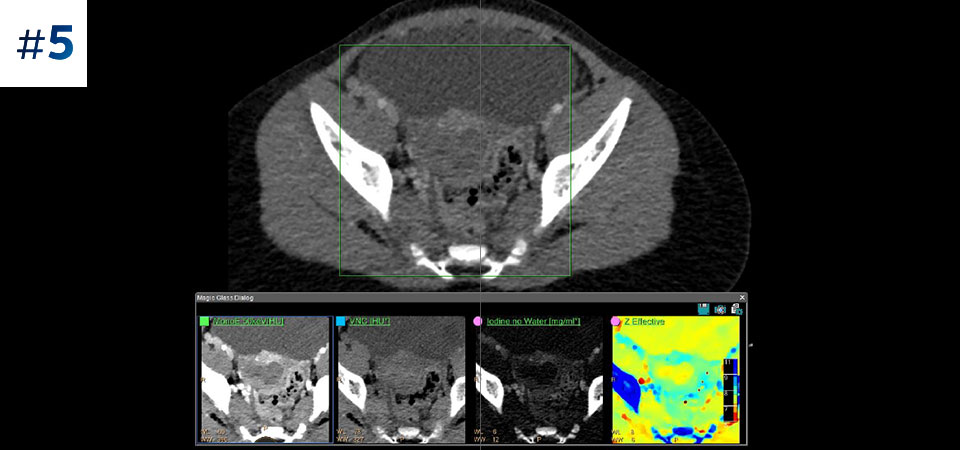

Scan as usual A single scan for fast, low-dose conventional and spectral data for every patient, every time.

Always available 100% spectral, 100% of the time for results that are always available on-demand, even retrospectively.

Reduced follow-up exams Improved tissue characterization and visualization may reduce the need for follow-up scanning for sub-optimal exams and incidental findings.

Go beyond conventional CT. See how layers of spectral-detector results can enhance your diagnostic confidence.

See the difference between spectral-detector CT and conventional CT